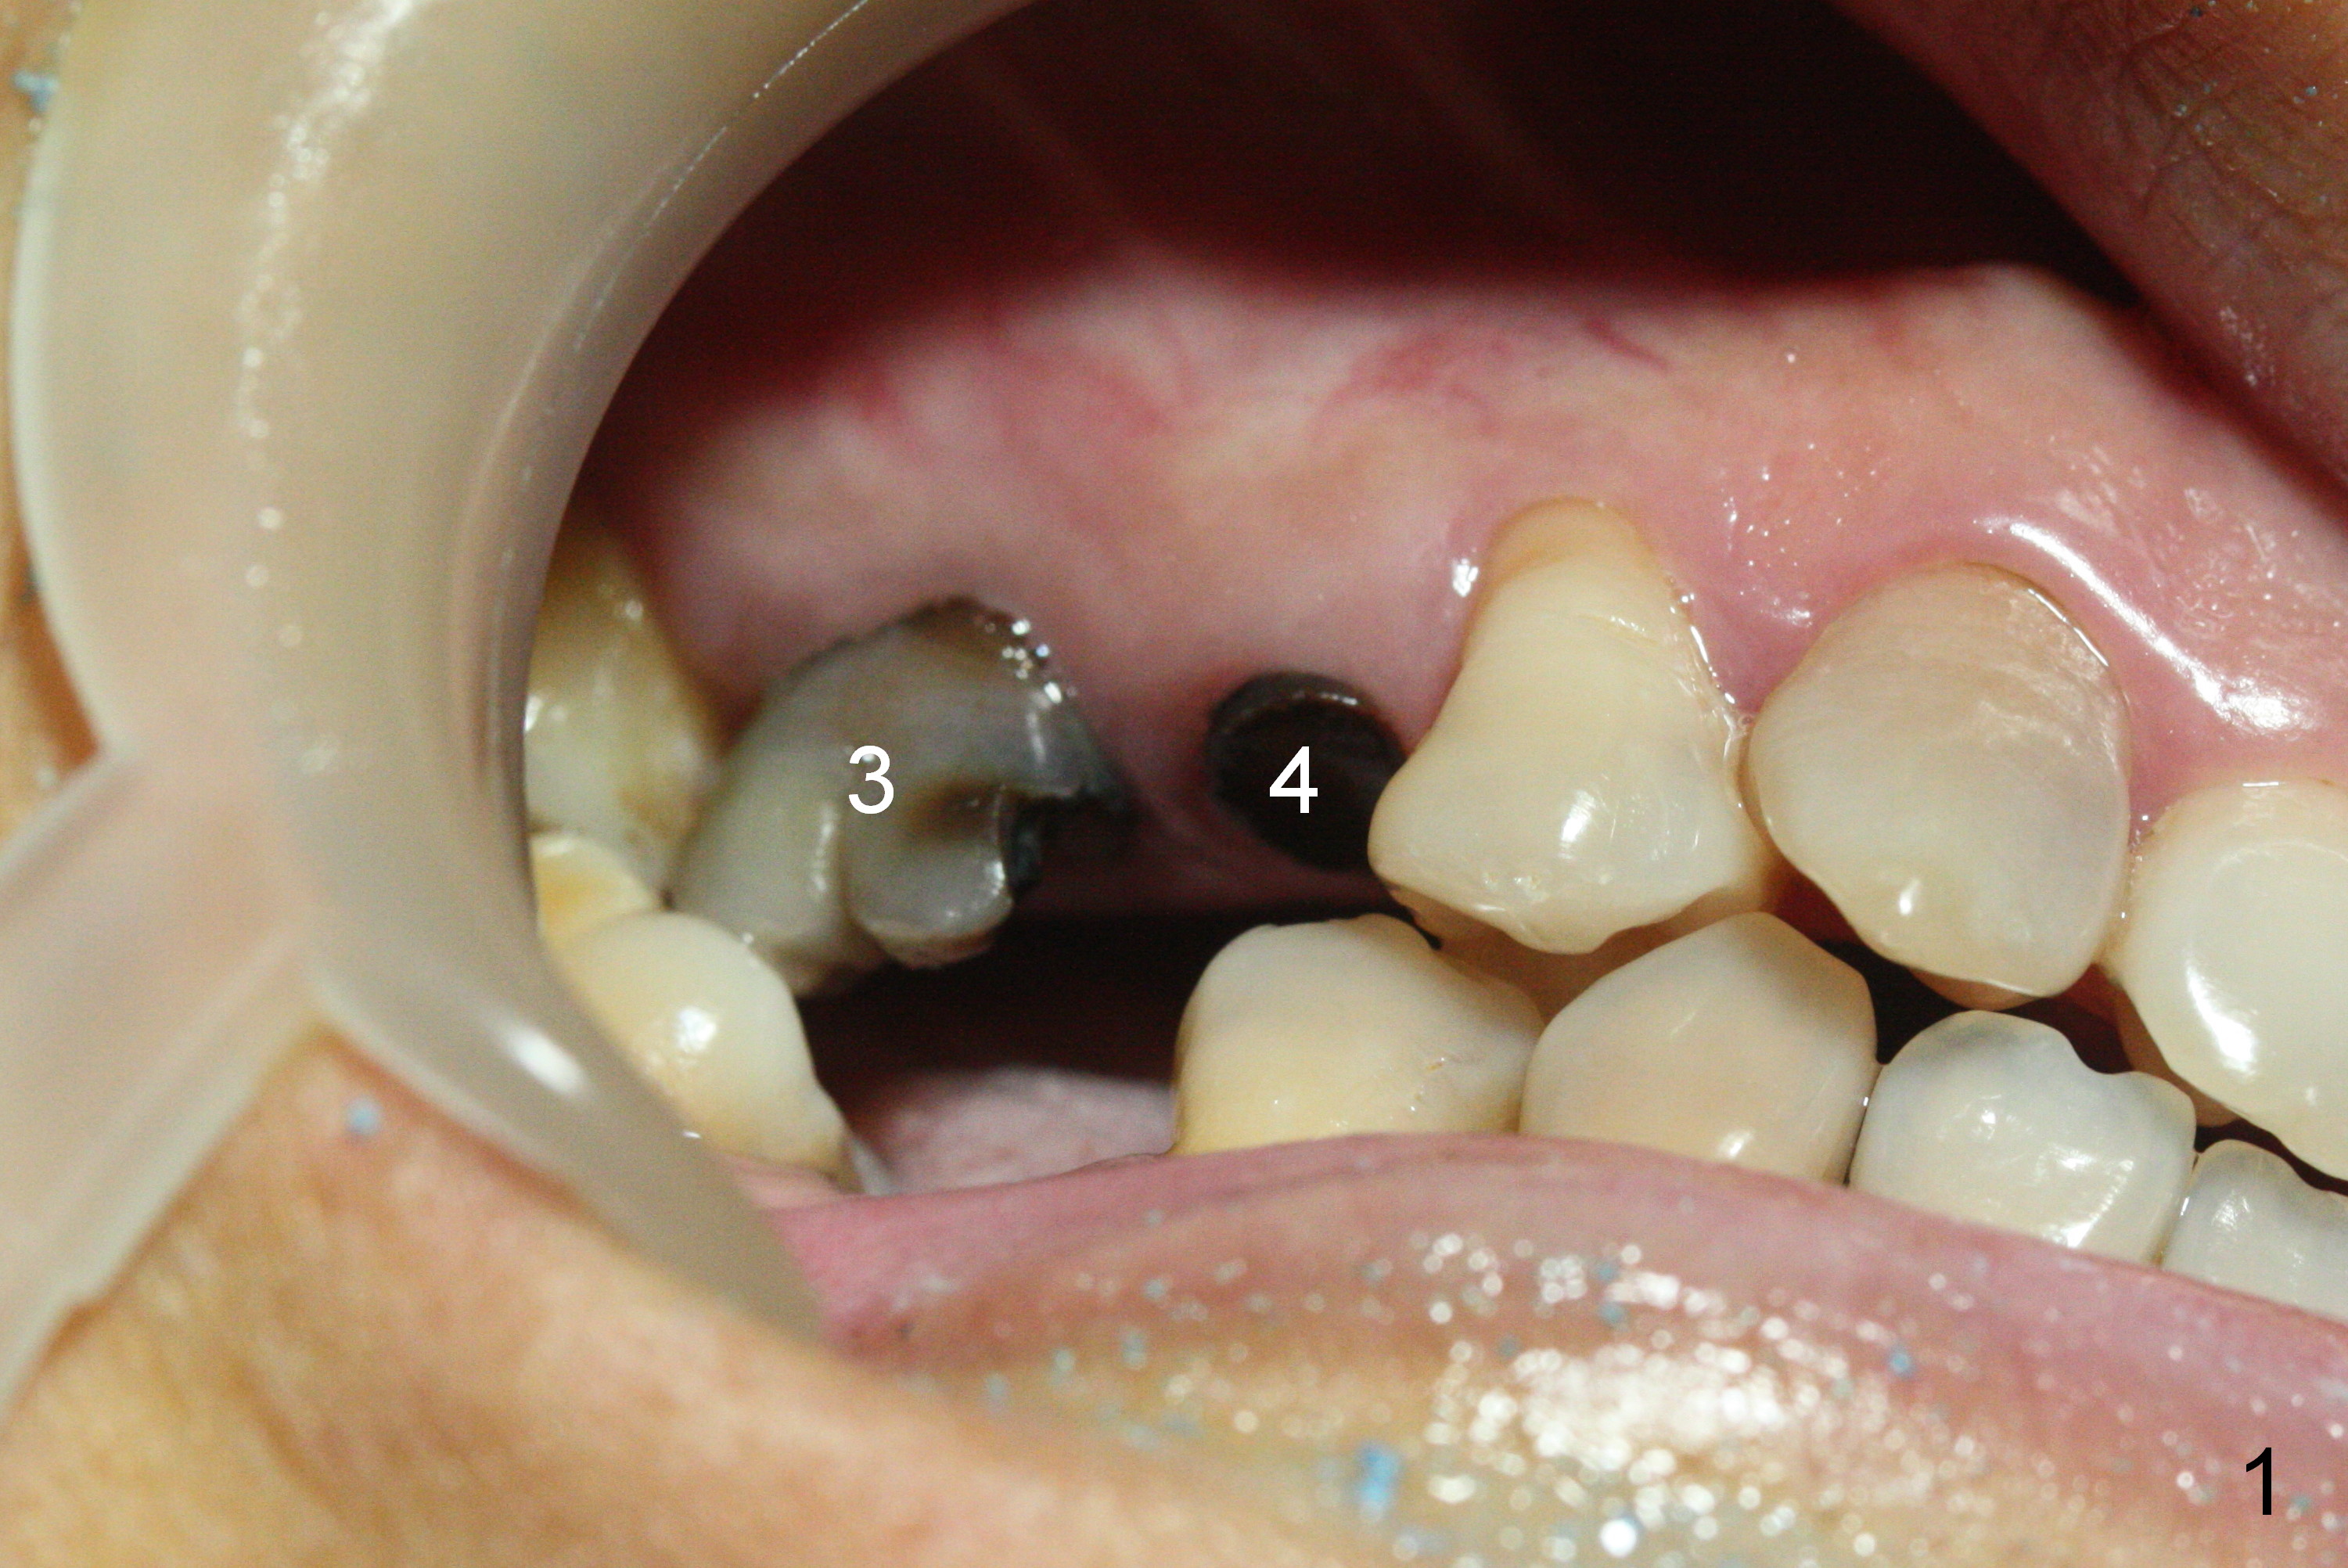

After extraction, osteotomy is established in the septum of #3 and the mesial slope of the shallow socket of #4 (Fig.2 red dashed line) for 11 and 13 mm deep, respectively. Since the septum is sloped palatally, a series of Magic Drills (MD) are used. A single large MD may wobble in the slope. By the time MD 3.8 mm is used, there is perforation palatally. The insertion torque of 4.5x13 mm IBS implant is less than 30 Ncm (Fig.3). In retrospectively, the osteotomy should have been initiated more buccally or deeper, since there is fair amount of clearance from the sinus floor (Fig.5 ^). The implant at #9 is 3.8x16 mm.

In contrast, osteotomy at #4 is finished with a single MD 3.3 mm. A 4x13 mm implant is placed with more than 50 Ncm. Pair abutments are immediately placed (6.5x4(3) and 4.5x4(3) mm) for splinted immediate provisional. The remaining socket (Fig.4 red dashed line) is filled with mixture of allograft, autogenous bone and Osteogen (*).